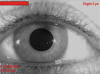

– Establecimiento del patrón de referencia.- Consiste en el registro de una imagen fotográfica del patrón del iris de cada ojo, en base al cual posteriormente podremos analizar los movimientos torsionales (fig. 4).

Fig. 4: Imagen de referencia para estudios torsionales.

– Estudios torsionales.- Podemos realizar cualquier tipo de movimiento ocular obteniendo de forma dinámica el registro de los movimientos que ocurran en ambos ojos, en cualquiera de los tres ejes.